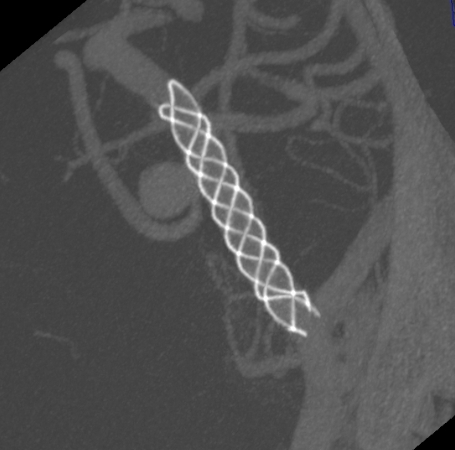

支架部分释放后复查造影示支架位置良好,缓慢完全释放支架,支架打开良好,复查造影示支架位置良好,完全覆盖瘤颈,贴壁佳,瘤囊内可见造影剂滞留明显,OKM分级A3。

Vaso CT显示 畅医达(Choydar)血流导向装置 位置良好,完全覆盖瘤颈,长轴及横轴薄层均显示支架贴壁良好。